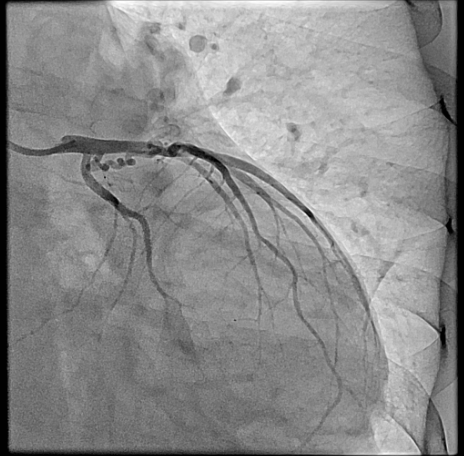

Right heart catheterization revealed a pulmonary capillary wedge pressure of 19 mmHg and mean pulmonary artery pressure of 47/27 mmHg. Pulmonary vascular resistance was 3.06 Wood units, with cardiac output of 4.9 L/min and Qp/Qs ratio of 1.24. Coronary angiography showed patent left main, LAD, and circumflex arteries. A small proximal LAD fistula and a large RCA fistula, both draining into the pulmonary artery, were identified.

The procedure was performed via left radial artery access. The right coronary fistula was engaged with a 6F AL1 guide catheter. A 5F microcatheter advanced an ASAHI Sion Black wire into the fistula tract. Given the fistula¡¯s large size and high flow, a two-device closure strategy was employed. A 7-mm AMPLATZER Vascular Plug 4 was initially deployed proximally, achieving partial flow reduction. To ensure complete occlusion, an 8-mm AMPLATZER Vascular Plug was subsequently positioned at the ostium. Final angiography confirmed marked flow reduction in the fistula while preserving native RCA flow. The small LAD fistula was left untreated due to minimal shunting. The procedure was completed without complications, and radial hemostasis was achieved.